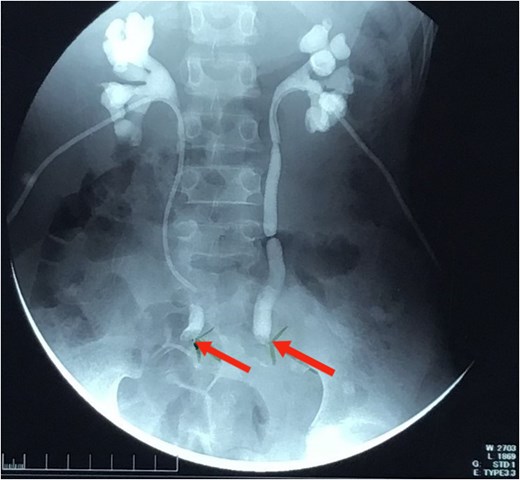

An 11-year-old Sudanese male presented with a year-long history of intermittent lower abdominal pain, altered bowel habits, and weight loss. Four months prior to presentation, he experienced minimal, painless rectal bleeding. Later, progressive urinary symptoms culminated in oliguria. Evaluation revealed bilateral hydroureter and hydronephrosis, necessitating bilateral percutaneous nephrostomy placement after failed attempts to insert JJ stents (Fig. 1). Previously, the patient underwent an appendectomy for presumed acute appendicitis but his symptoms persisted. The family history was negative for CRC or related conditions.

Nephrostogram showing bilateral hydroureter with complete ureteric obstruction and no dye in the bladder. The two arrows indicate complete bilateral ureterovesical obstruction.